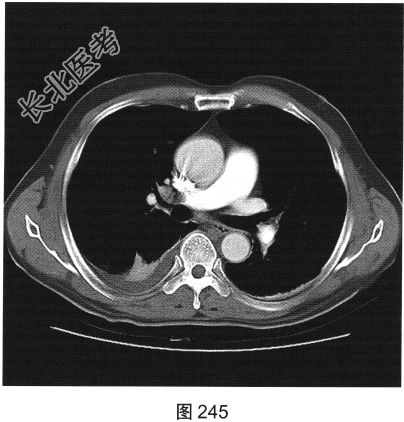

- 多项选择题2.[提示]一该患者行CT肺动脉成像,如图245所示。CT检查可见哪些阳性影像学表现( )

A、CT示右肺部分肺组织肺梗死

B、CT示右肺动脉主干栓子

C、CT示右侧胸腔少量积液

D、CT示肺动脉主干扩张

E、CT示右肺部分肺组织不张

F、CT示主动脉内夹层形成